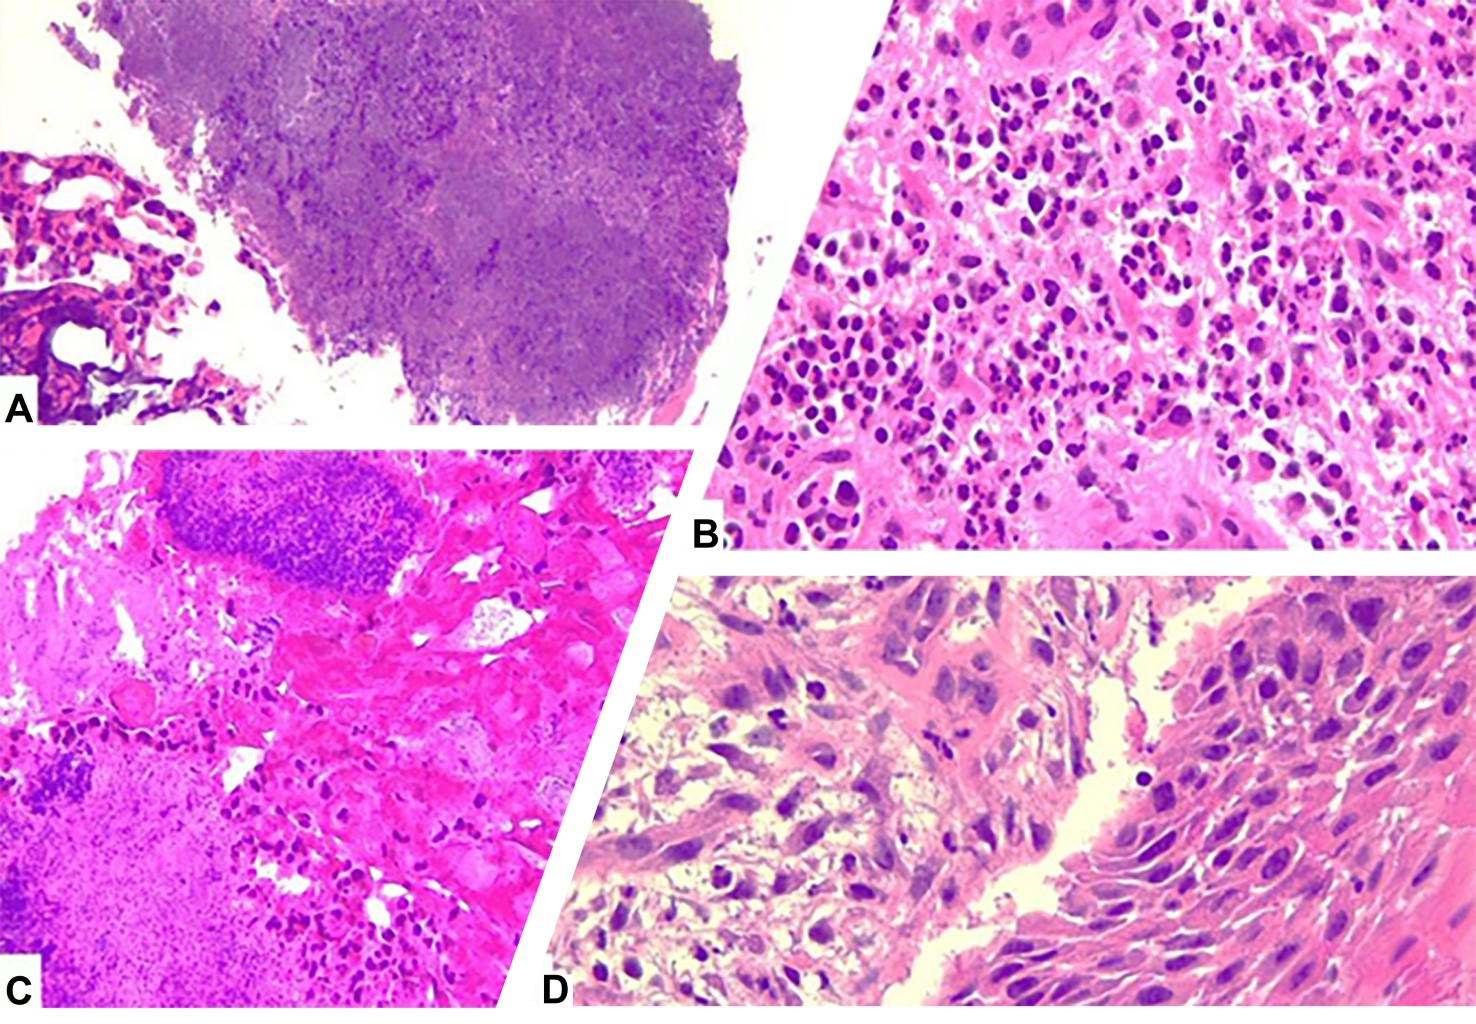

Se realizó una nueva toma de biopsia antes del retiro del tumor. Los resultados de la biopsia de mucosa oral y de hueso mandibular señalaron: mucosa oral con acentuada inflamación, zonas de proliferación vascular capilar y presencia de microorganismos morfológicamente consistente con actinomices (Figura 3). Como consecuencia de resultados compatibles con una infección por actinomices, se decidió interrumpir el procedimiento quirúrgico y comenzar un tratamiento antimicrobiano dirigido por el equipo de infectología. Para finalizar la anestesia, se realizó la reversión farmacológica mediante la administración de sugammadex de 200 mg, y se retiró el tubo endotraqueal después de aspirar las secreciones, con la presencia de reflejos de la vía aérea y una adecuada recuperación de la paciente en el postoperatorio inmediato. Se dio de alta a la paciente al día siguiente con tratamiento antimicrobiano específico y seguimiento por la consulta externa.

Figura 1

Figura 2

Figura 3

Figura 4